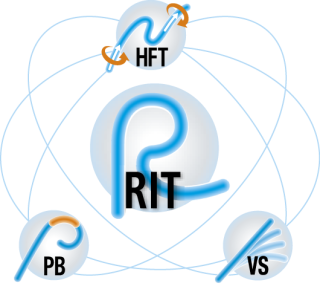

- Технология «отзывчивого введения» RIT упрощает процедуру введения и прохождения анатомических особенностей толстой кишки. Это запатентованная разработка Olympus специально для колоноскопии. RIT сокращает время процедуры и уменьшает дискомфорт пациента, в том числе необходимость в седации. В основе «отзывчивого введения» лежат 3 принципа: HFT точная передача усилий при проталкивании и вращении, PB пассивно-изгибаемая часть для прохождения изгибов толстой кишки и VS переменная жесткость. Подробнее о технологии RIT вы можете узнать в разделе «Видео» этого продукта.